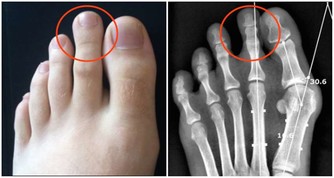

口腔潰瘍的情況下密切接吻有可能感染艾滋病。

艾滋病的傳染要滿足三個條件:傳染源,傳播途徑,易感人群。

即使會傳染,但實際上有很多前提條件:

1.一方確實感染了艾滋病毒;

2.感染者沒有經過任何抗病毒治療;

3.口腔有潰瘍出血。

即使三個條件都滿足,少量艾滋病毒進入身體,病毒量也通常達不到染病的程度。而且,人體自身的免疫功能,面對艾滋病毒也會啟動防護機制。

因此,口腔潰瘍出血在概率上的確存在感染的可能,但被感染的機率微乎其微。

至於很多人擔心,有口腔潰瘍的情況下接吻感染,就​​算真的發生,也是因為血液暴露,歸於血液傳播,而不能說接吻是艾滋病的一個傳播途徑。